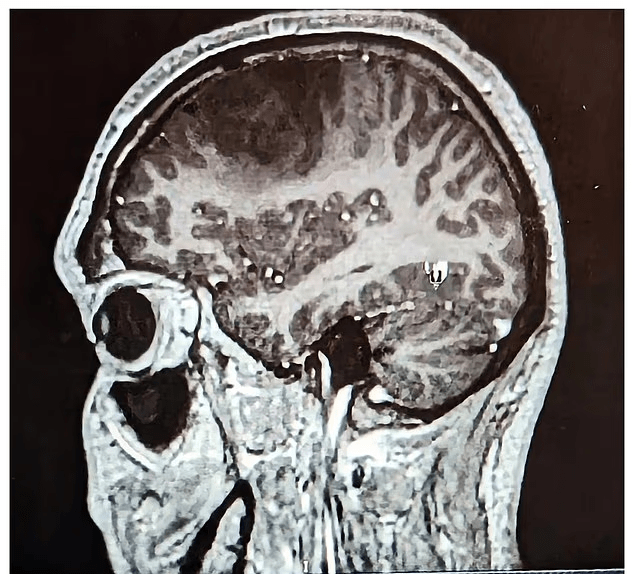

Por ajo që nuk e priste ishte zbulimi i një tumori në tru, sa një dardhë, një gliomë me zhvillim të ngadaltë, që po rritej pa u vënë re.

“Bënë një skanim për të parë nëse kisha gjakderdhje të brendshme ose tronditje, që me siguri e kisha,” – shtoi ai. “Prisja të më thonin diçka të tillë, por në vend të kësaj, më thanë: ‘kemi një lajm të mirë dhe një të keq’. Lajmi i mirë ishte se nuk kishte gjakderdhje, por lajmi i keq ishte se kishin zbuluar një tumor primar në tru.”

Megjithëse mban një qëndrim pozitiv, Connor u detyrua t’i nënshtrohej disa ndërhyrjeve të vështira kirurgjikale. Në shkurt 2023 iu nënshtrua një kraniotomie, ku mjekët hoqën 70% të tumorit. Por operacioni duhej ndalur për shkak të afërsisë me zonën e të folurit në tru – nëse do të vazhdonin, ai do të humbiste përgjithmonë aftësinë për të komunikuar.

Në një kontroll MRI në shkurt, mjekët vunë re zona të reja në tru që ndizeshin gjatë skanimit – kishte një rritje të re. Kjo e detyroi Connor-in të fillojë 6 javë terapi me rrezatim (radioterapi), prej të cilave ai ka kaluar katër, e më pas do të ndjekë një trajtim me kimioterapi – çka e detyroi të largohet sërish nga puna.